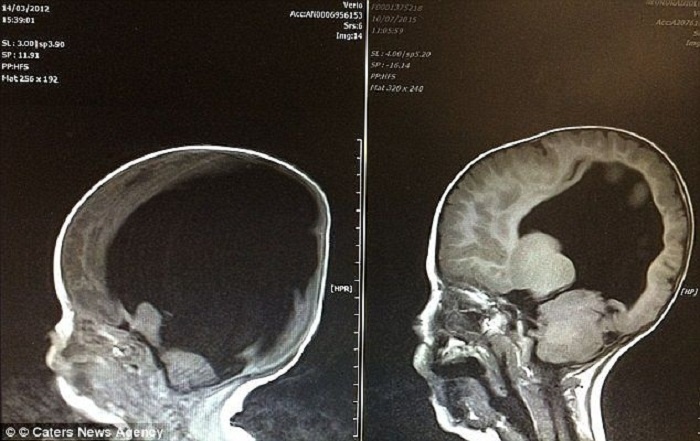

Так изменился объём мозга Ноя всего за несколько лет

Когда Ной появился на свет, врачи сообщили родителям: мозг малыша составляет всего 2 процента от нормы. При этом кроха жив и хватается за возможность есть и дышать.

Операция прошла успешно, а вскоре последовали отличные новости. Оказалось: головной мозг Ноя никуда не делся, он просто был сильно сдавлен кистой. Это открытие дало Шелли и Робу надежду на то, что их малыш всё-таки сможет жить нормальной жизнью.

За несколько лет головной мозг мальчика восстановился и достиг почти 80 процентов от нормального объёма. Но ещё больший шок ждал всех наблюдавших за историей через пару лет: Ной научился говорить, читать, считать и писать. Мальчик мало чем стал отличаться от нормотипичного ребенка.